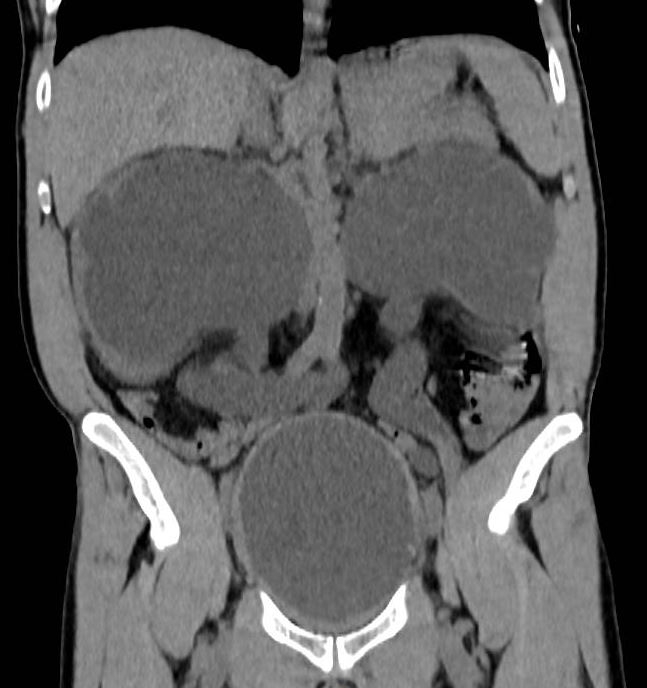

Un scanner sans injection est réalisé.

Question 8 : Parmi les propositions suivantes, lesquelles sont justes au vu des résultats du scanner ?

Le scanner montre une uretéro-hydronéphrose bilatérale avec globe vésical et dilatation importante des cavités pyélocalicielles. Sur la coupe axiale, on voit une hypertrophie de la prostate (surtout le lobe médian) compatible avec une hypertrophie bénigne de la prostate. Le diagnostic de cancer ne peut être éliminé mais les données du toucher rectal ne sont pas en faveur.